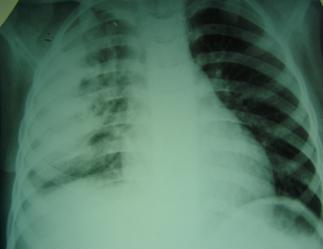

Диагностика

Диагностика пиоторакса осуществляется путём проведения комплексного физикального, инструментального, а также лабораторного обследования. Осмотр пациента помогает выявить отставание одной половины грудной клетки при дыхании (с поражённой стороны), а также выбухание и расширение межреберий. На рентгенограмме органов грудной клетки обнаруживается интенсивное затемнение. Для определения размеров и формы эмпиемы плевры выполняется плеврография с водорастворимым контрастом, который вводится в плевральную полость. В некоторых случаях также применяется ультразвуковое обследование. Для окончательного подтверждения диагноза пиоторакса проводится пункция плевральной полости с последующим микроскопическим и бактериологическим исследованием плеврального выпота.